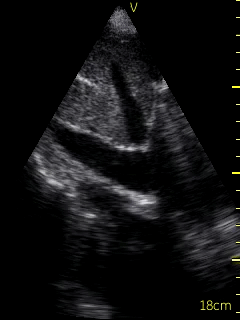

A bedside echocardiogram (VScan, GE) showed evidence of severe left ventricular and right ventricular thickening. Both atria were severely dilated. The mitral, tricuspid, and aortic valves appeared thickened. Myocardial speckling was not appreciated. Both the left and right ventricular function appeared to be moderately impaired.